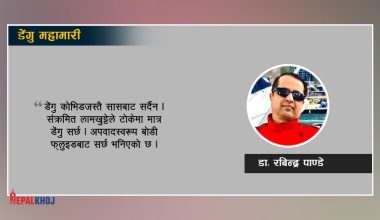

पाकिस्तानमा डेङ्गुको प्रकोप, ३० हजारभन्दा बढी सङ्क्रमित

पर्वत अस्पतालमा डेंगु परीक्षण गर्न कीटको अभाव

कर्णालीमा ५४१ जनालाई डेंगु, मुटुरोगी बढ्दै

डेंगु सम्बन्धि केही कुरा